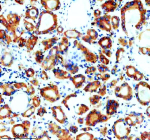

Immunohistochemical staining of SNX2 using anti-SNX2 antibody. SNX2 was detected in a paraffin-embedded section of human colon cancer tissue. Heat mediated antigen retrieval was performed in EDTA buffer (pH 8.0, epitope retrieval solution). The tissue section was blocked with 10% goat serum. The tissue section was then incubated with 2 ug/ml rabbit anti-SNX2 antibody overnight at 4oC. Peroxidase Conjugated Goat Anti-rabbit IgG was used as secondary antibody and incubated for 30 minutes at 37oC. The tissue section was developed using an HRP secondary and DAB substrate.